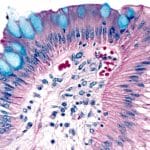

Alcian Blue Solution

Acid (simple, or non-sulfated) – Are the typical mucins of epithelial cells containing sialic acid. They stain with PAS, Alcian blue at pH 2.5, colloidal iron, and metachromatic dyes. They resist hyaluronidase digestion. Acid (simple, mesenchymal) – These contain hyaluronic acid and are found in tissue stroma.